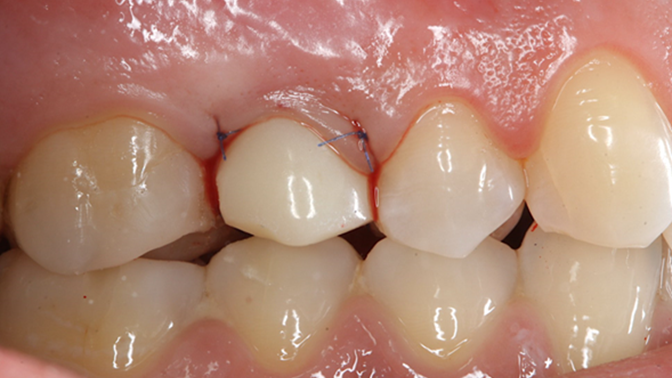

Clinical case: AnyRidge immediate loading

- Courtesy of Dr. Andres Paraud Freixas, Chile -

Keywords

AnyRidge, ISQ value, initial stability, immediate loading, KnifeThread, maxillary anterior, Mega ISQ, Dr. Andres Paraud Freixas

“Patient’s smile was recovered on the day of surgery

with reliable & highly-aesthetic results using AnyRidge & R2GATE. ”